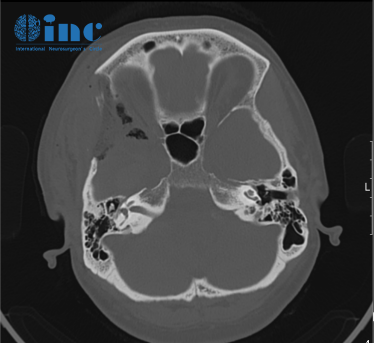

(術(shù)后CT)